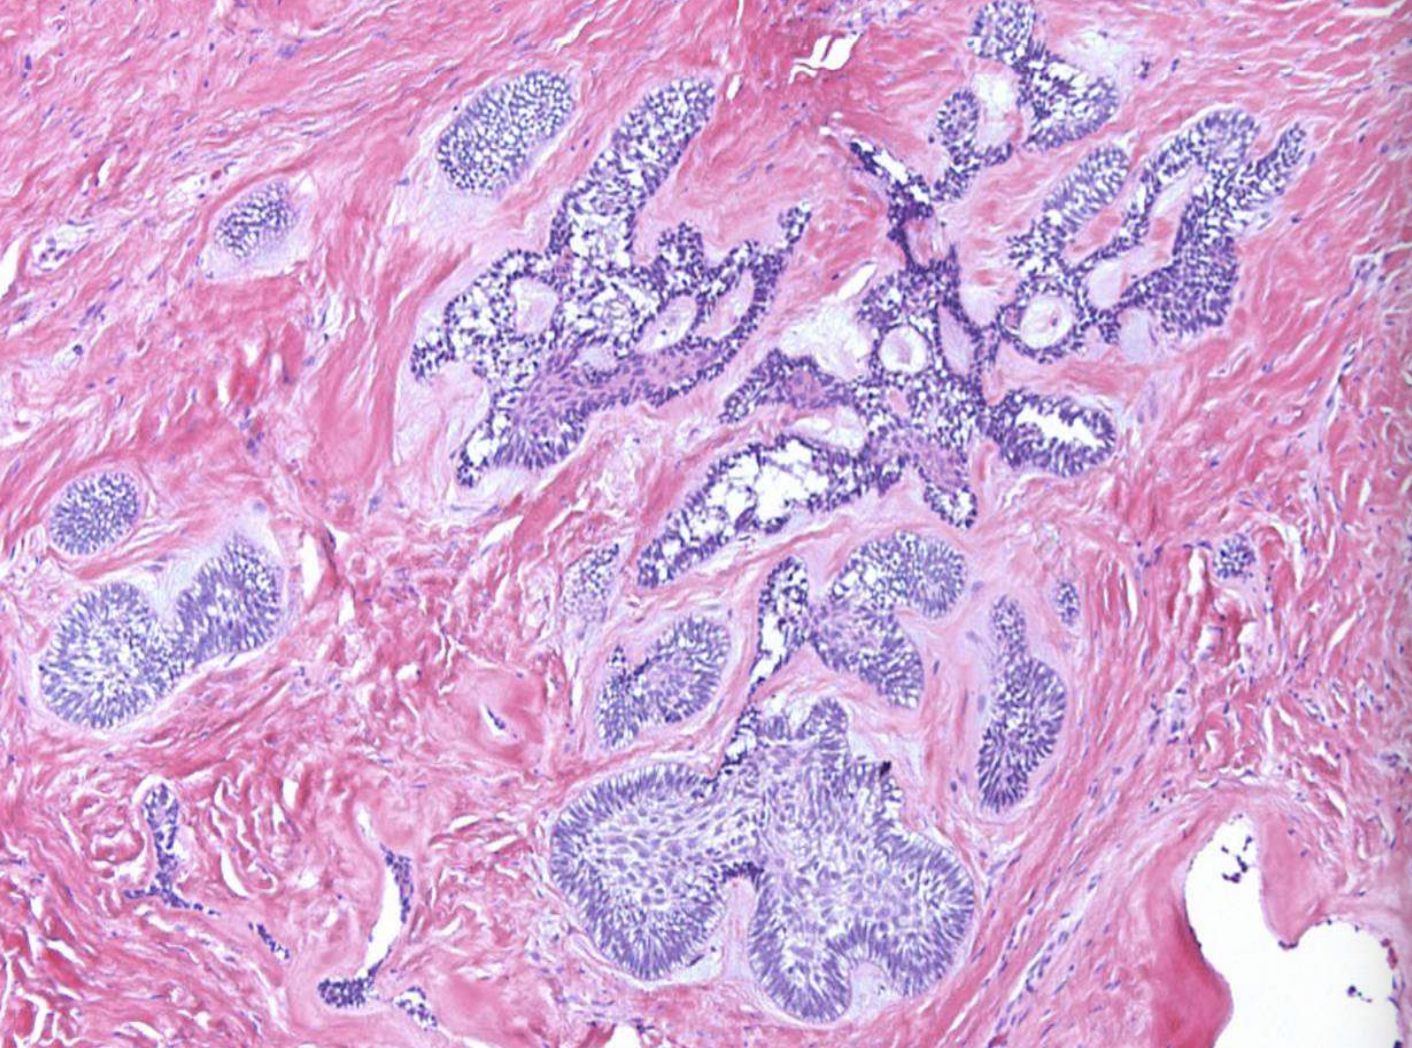

what are histopathologic patterns of ameloblastomas?

• Follicular

• Plexiform

• Acanthomatous

• Granular cell

• Basal cell

• Desmoplastic

what are the key microscopic histopathologic appearance of ameloblastomas?

Follicular pattern

Nests of epithelium

Island centers resembling stellate reticulum

Peripheral columnar cells with nuclei polarized opposite basement membrane (sub-nuclear vacuolization)

Mature fibrous background

ameloblastoma (Island centers resembling stellate reticulum)